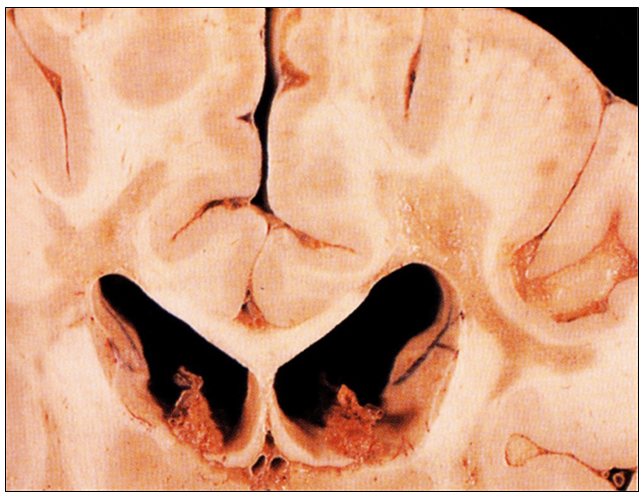

50세 여자가 교통사고로 사망하여 부검하였다. 수년간 손의 감각 이상, 다리의 허약감, 시각 장애 등의 증상이 악화와 호전을 반복하였다고 한다. 뇌에서 사진과 같은 소견이 보였다. 진단은?

[다발경화증, multiple sclerosis]

• 다발성 경화증은 뇌 또는 척수의 demyelination이 일어나는 자가면역질환이다.

• Episodic하게 찾아오는 신경학적 증상은 중추신경계에서 시간차를 두고 다발적으로 나타나는 백질 병변을 동반한다.

• 임상증상은 중추신경계의 어디를 침범하는가에 따라 ataxia, nystagmus, motor and sensory impairment 등이 악화되었다 호전하는 등 다양한 양상을 가진다.

• 초기에는 한쪽의 시력이 상실되는 optic neuritis가 나타날 수 있다.

• 병변의 육안적 소견은 회색/갈색을 뛰는 불규칙적 모양의 판으로, 주변 조직과의 경계가 뚜렷하다.

• 만약 병변이 active하다면 조직검사에서 foam cell (지방으로 가득 차 비대해진 대식세포)을 관찰할 수 있다 (사진 A).

• 사진 B는 말이집을 염색하는 luxol fast blue stain, 사진 C는 축삭을 염색하는 면역염색 결과로, 다발성 경화증 환자에서 말이집은 파괴되지만 축삭 자체는 보존됨을 확인할 수 있다.